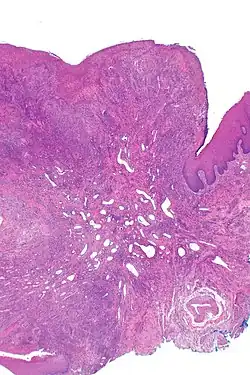

| Eosinophilic ulcer of the oral mucosa – H&E stain | |

Eosinophilic ulcer of the oral mucosa (also known as traumatic eosinophilic granuloma[1]) is a condition characterized by an ulcer with an indurated and elevated border.[2] The lesion might be tender, fast-growing and the patient often not be aware of any trauma in the area.